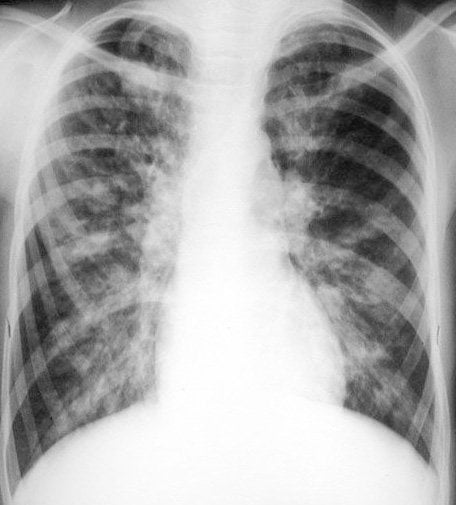

| Дыхательная | Плеврит, пневмония, новообразования проявляются болями различной интенсивности в грудном отделе. К сопутствующим симптомам относятся одышка, кашель, хрипы, повышение температуры тела |

Установить причину болей в грудном отделе позвоночника позволяет проведение рентгенографии, МРТ, УЗИ, КТ.

При жалобах на боли в сердце пациентам назначается ЭКГ, в том числе на фоне нагрузки на беговой дорожке для исключения стенокардии. Женщинам показана маммография, так как боли могут быть спровоцированы доброкачественными или злокачественными новообразованиями в молочных железах.